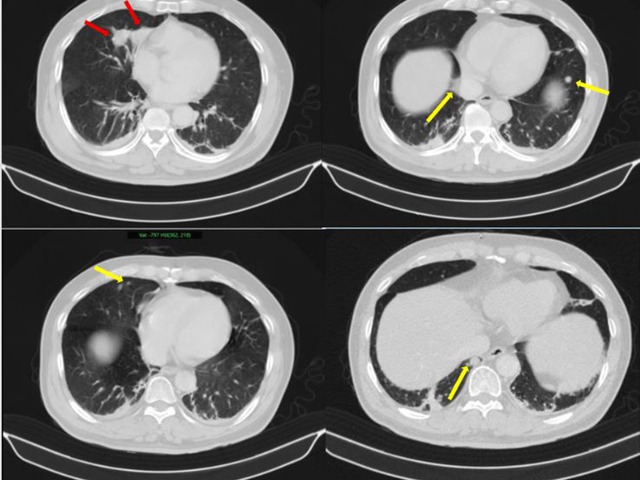

Người đàn ông phát hiện mắc hai bệnh ung thư cùng lúc- Ảnh 1.

Những hình ảnh bất thường trên phổi của bệnh nhân (Ảnh: BV Bạch Mai)